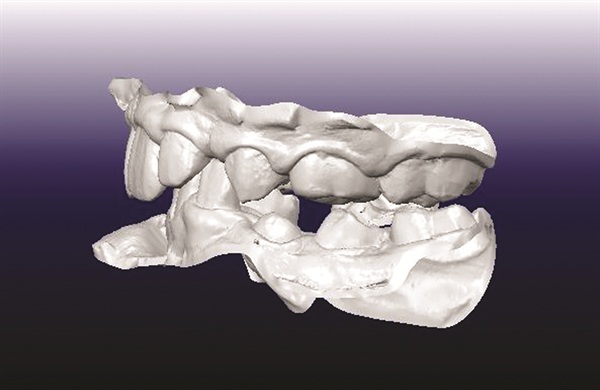

A 12-year-old male presented with severe Class II, deep bite, and significant crowding. The original poster was torn between two conflicting clinical pictures. Half the diagnostic findings pointed toward extraction: second molars impacted in the ramus, a blocked lower left canine, blocked maxillary canines, and a nearly full-step Class II relationship. The other half suggested non-extraction with vertical control to avoid deepening the bite further. The concern was that by the time crowding was resolved and the deep bite corrected, the incisors would be too flared for effective Class II correction without further proclination. The question posed to the forum was whether immediate upper first premolar and lower second premolar extractions were the best route forward (Figs. 1–11).

Fig. 3